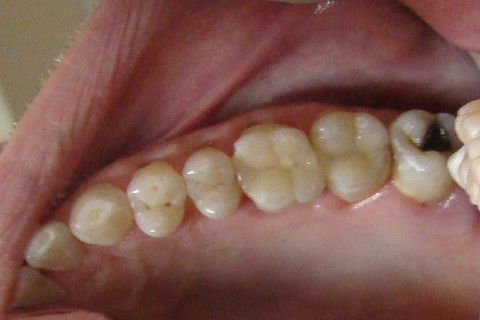

Paciente do sexo masculino, 45 anos , apresentou nos elementos 26 e 27 lesões de cárie.

Após remoção do tecido cáriado, tendo em vista a destruição de parte das coroas , optou-se pela realização das restaurações diretas através do uso de resinas compostas, FILTEK z 350 XT ( 3M - ESPE ).

Fotos do caso